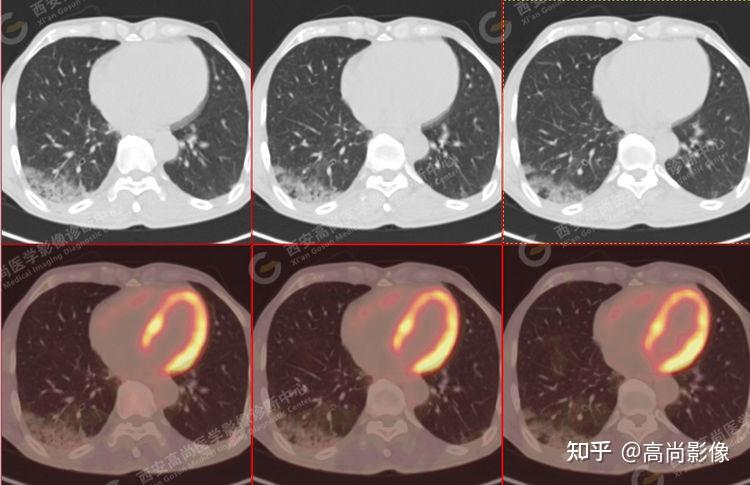

pet/ct病例—肺粘液腺癌,历经3年余终确诊【西安高尚医学影像诊断中心